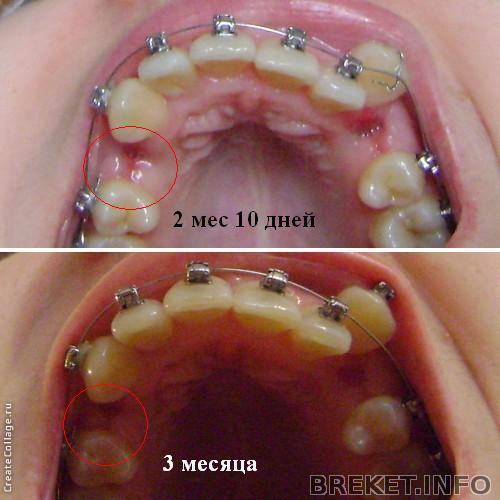

Решила отчитаться по результатам за 3 месяца - для многих эта дата считается значимой. Итак, что мы имеем: все еще первая дуга (менять уже точно 8 апреля), все еще неподключенный клык (на прошлом приеме его отвязали от дуги) и затягивающуюся дырку от четверки с одной стороны. Клык на этой стороне тянем эластичной цепочкой, но она чисто символическая, она болтается и почти не натянута. Ортша говорит, что так и надо, потому что если тянуть клык сильнее на тонкой дуге, зубы могут двигаться не так как надо. Так что клык по сути идет к пятерке сам, и неплохо идет (на фото видно, что расстояние сократилось)

А вот когда мне кажется, что ничего не меняется, я смотрю на этот коллаж

Мне кажется, или правда челюсть расширилась за 3 месяца?